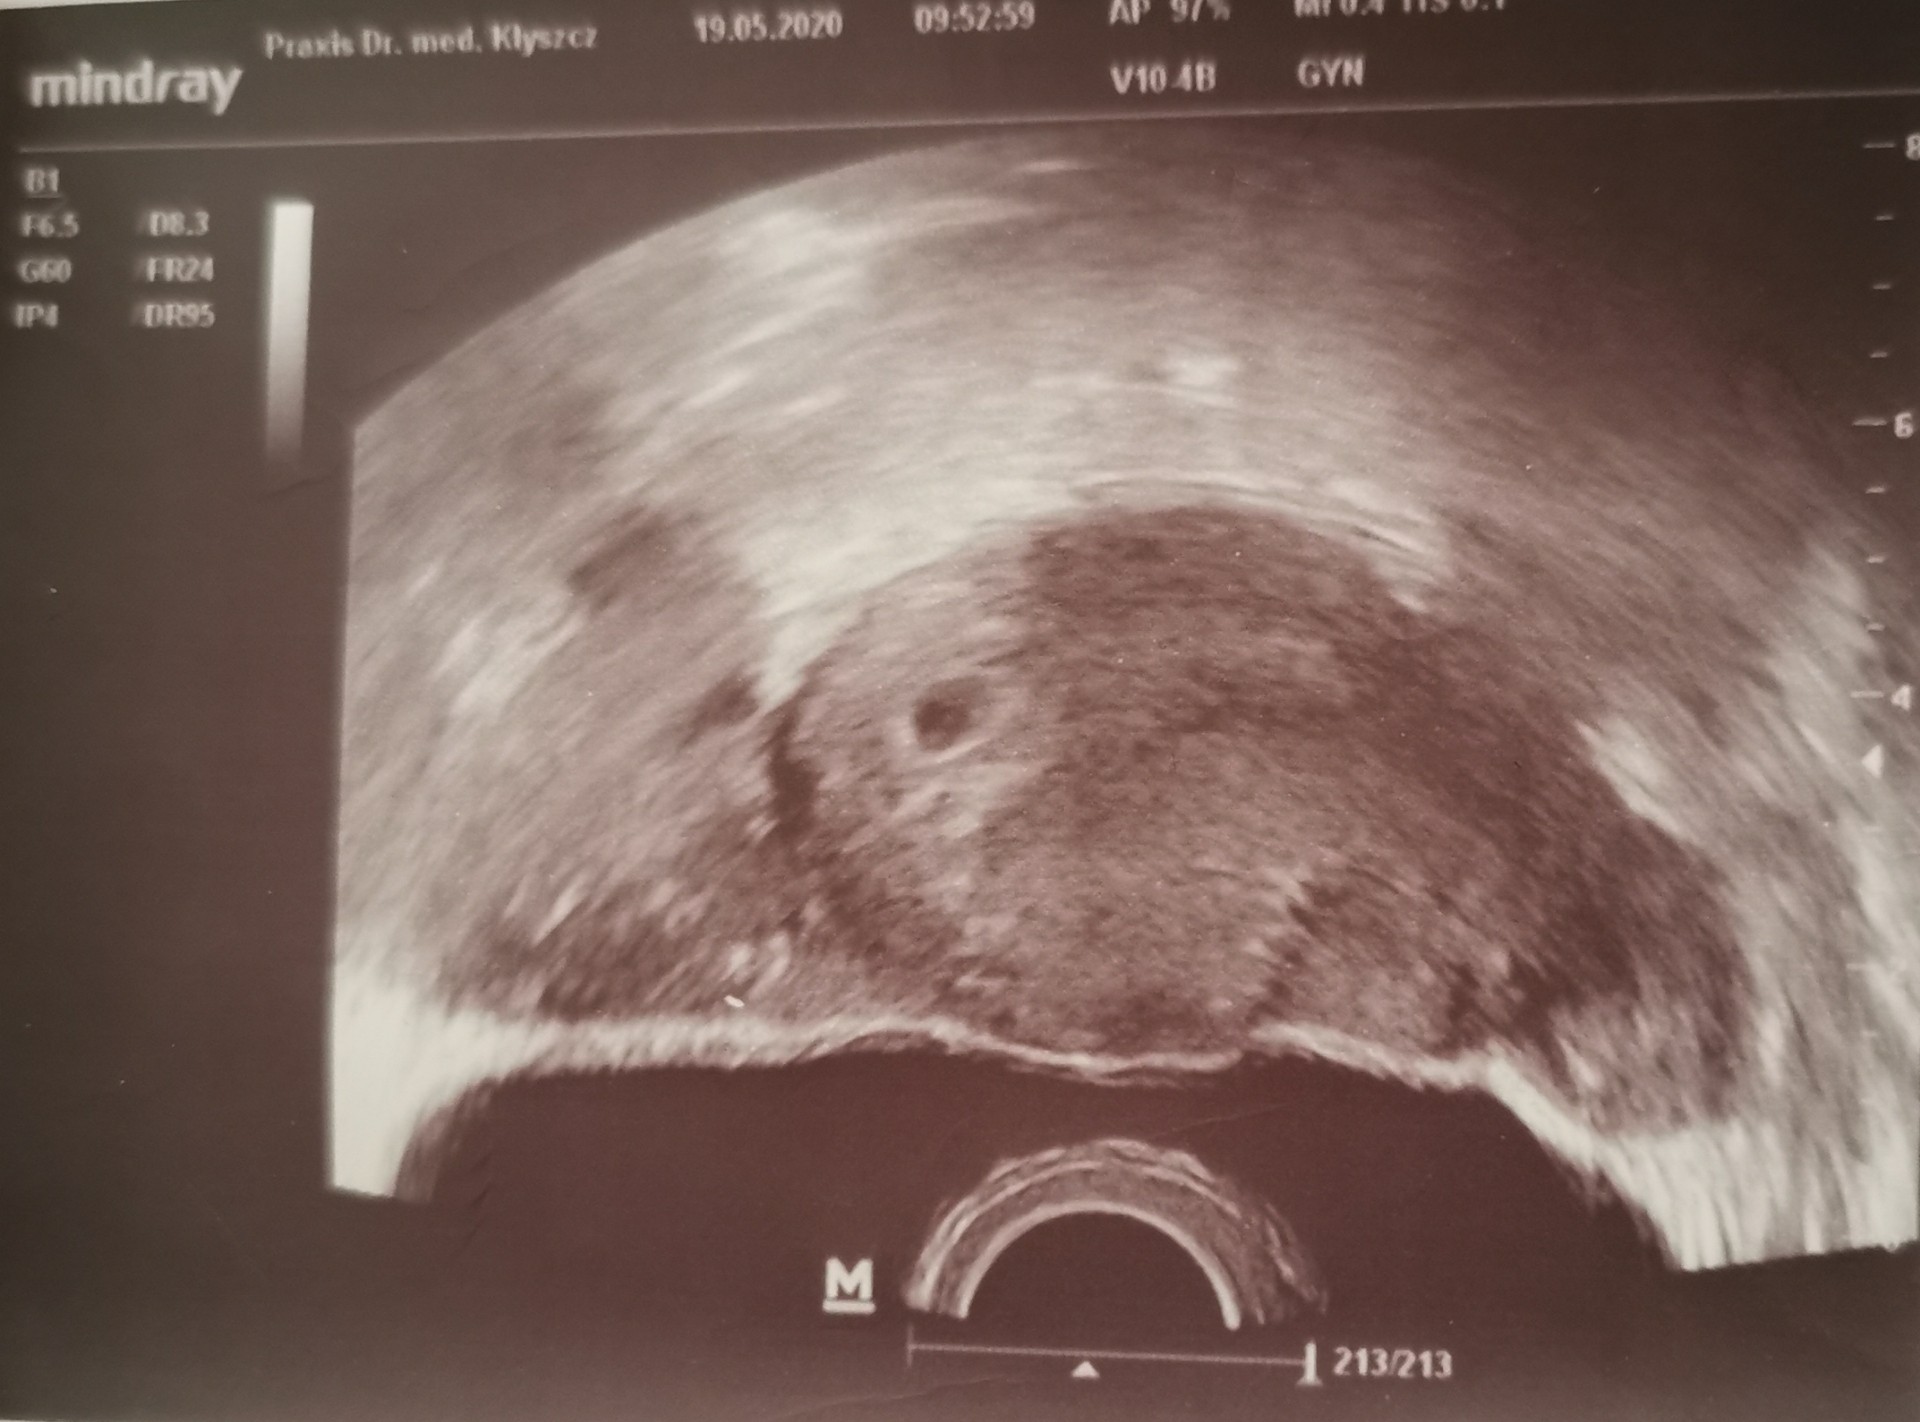

Dodam jeszcze zdjęcie z USG wtorkowego (19.05)